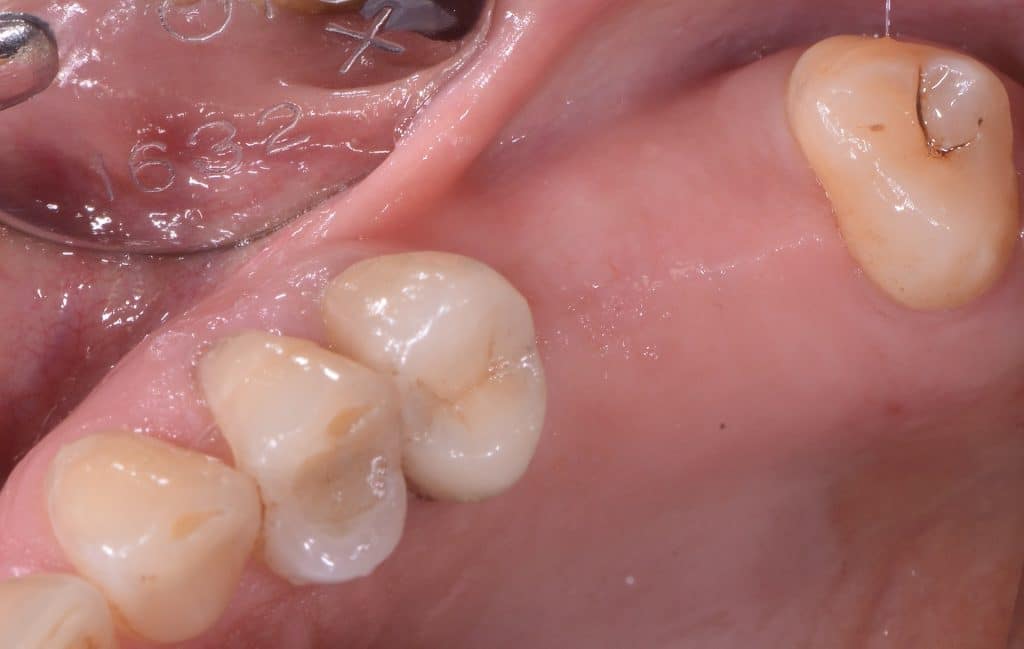

operating area, occlusal view